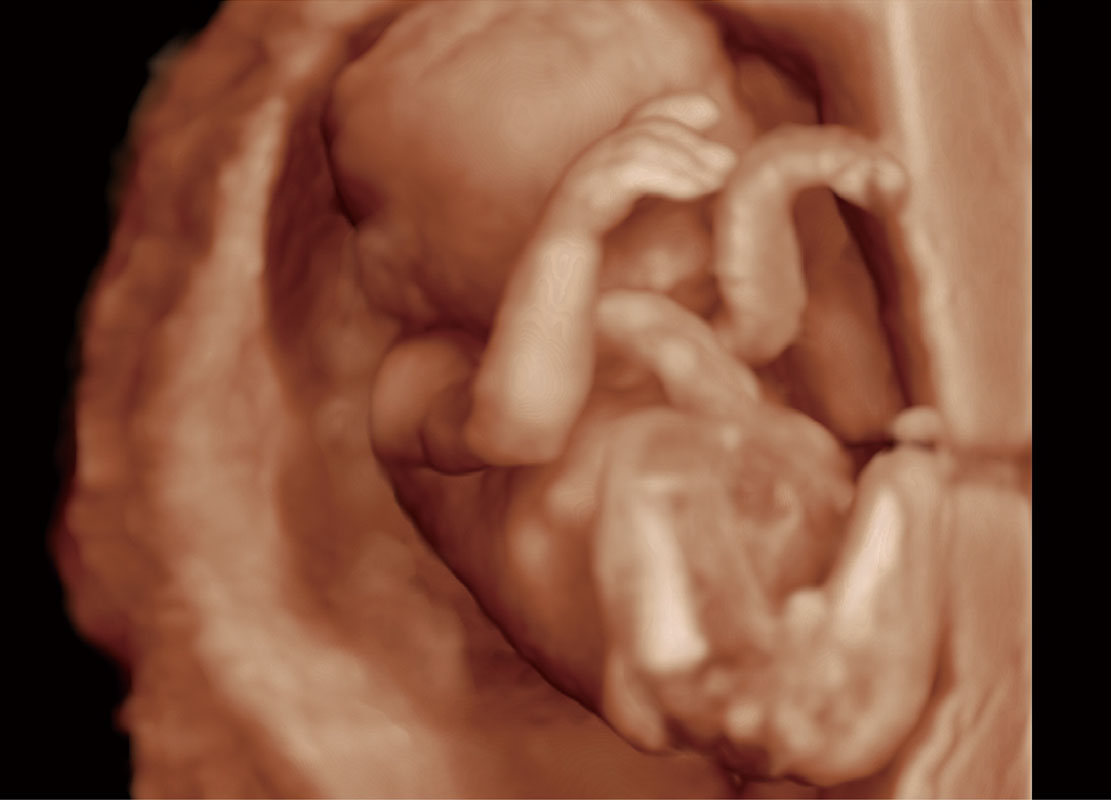

P60在胎儿早孕期超声筛查中为您带来优异的图像质量。

早孕-胎心

高分辨率容积成像-早孕胎儿

胎儿体循环

光影成像-孕囊